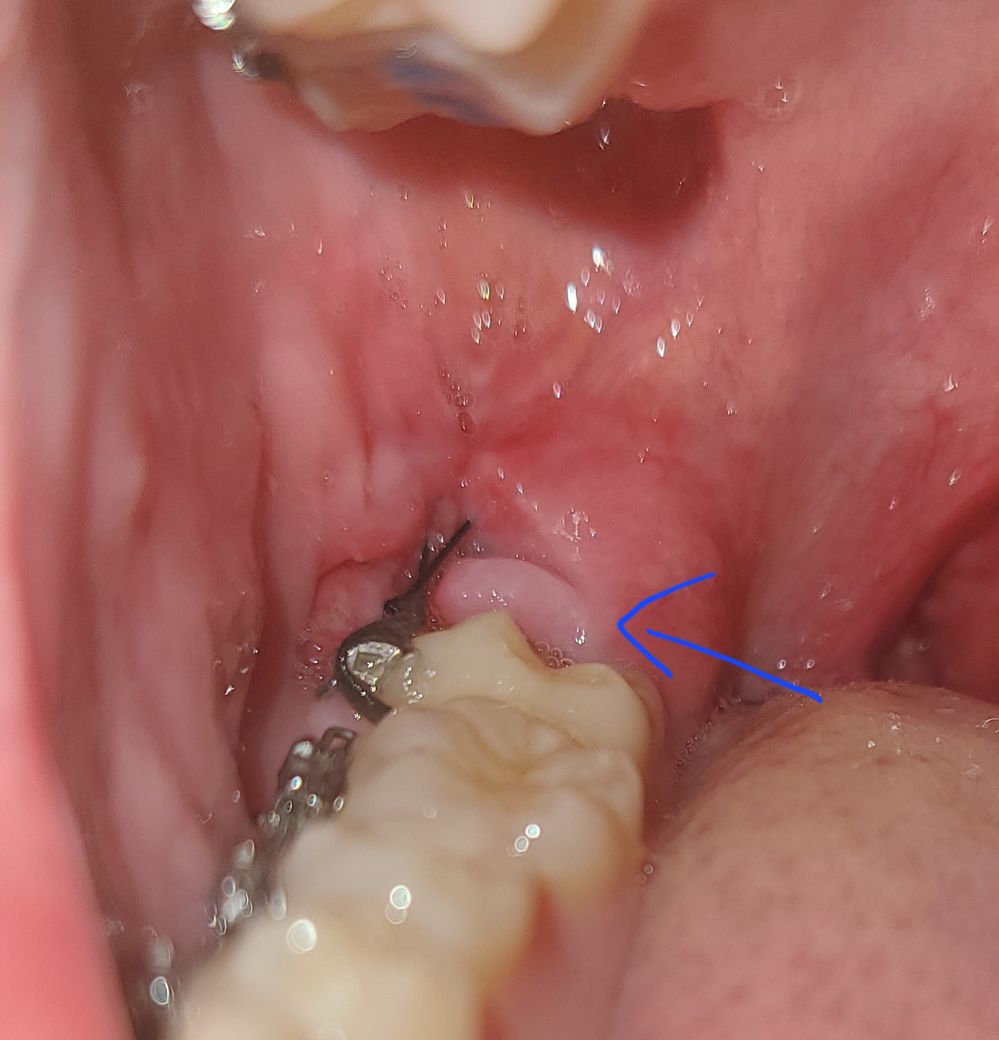

매복 사랑니 발치후 잇몸이 갈라진 것처럼 보여요.

저번주 금요일에 오른쪽 아래 매복사랑니를 발치했습니다. 일요일까진 안 이랬던거 같은데, 월요일날 아침에 일어나서 보니 화살표 친 부분의 잇몸이 갈라진 형태처럼 보이게 되었습니다. 혹시 실밥이 풀린건가요? 그 부위에 통증은 전혀없고, 처방받은 가글,물 음식물이 닿아도 따갑거나 아프진 않습니다. 이번주 토요일에 실밥제거를 하기로 되어있고 사정상 토요일까지 발치한 치과에 방문하기 어려운데, 치과에 방문하지 않아도 되는 문제인가요?

발치를 하고 나서는 해당부위에 잇몸이 갈라진것처럼 보일수 있습니다.

실밥이 풀린거 같진 않습니다. 사진상으로도 크게 문제가 있어 보지인 않으니 너무 걱정하지 않으셔도 될것같습니다.

원래의 모양이 어땠는지는 모르겠으나 잘 낫고 있는 모양새이며 잇몸의 상태도 좋아 보입니다.

사진상 잇몸은 치유 과정 중에 있는 것으로 판단됩니다. 별다른 증상이 없다면 굳이 그것 때문에 치과에 가거나 하실 필요는 없고 시간 될 때 실밥 제거만 하러 가시면 되겠습니다.